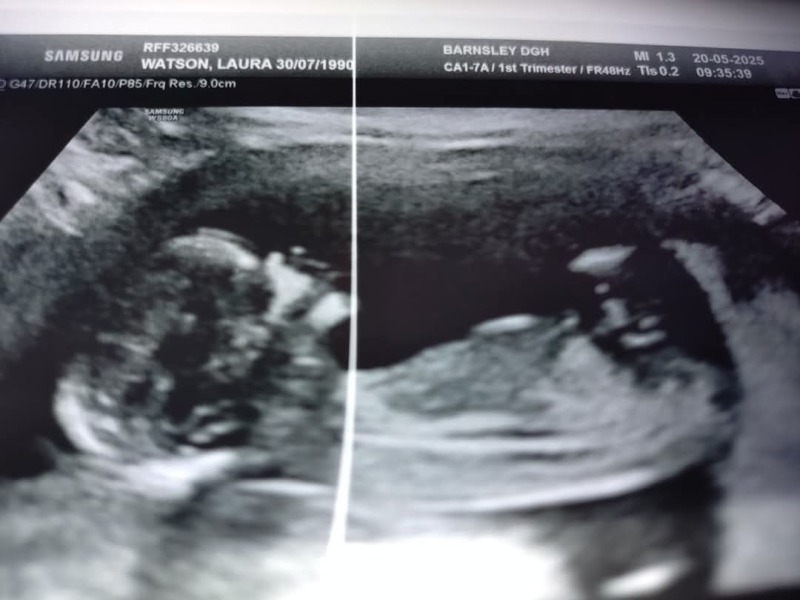

Flopsy145 · 12/07/2024 07:38

For reference this is my boys scan and it looks very similar so I would say boy. Im now 39 weeks and at my 36 week scan saw a very large pair of testicles so pretty certain it's a boy 😂

Leg or nub?